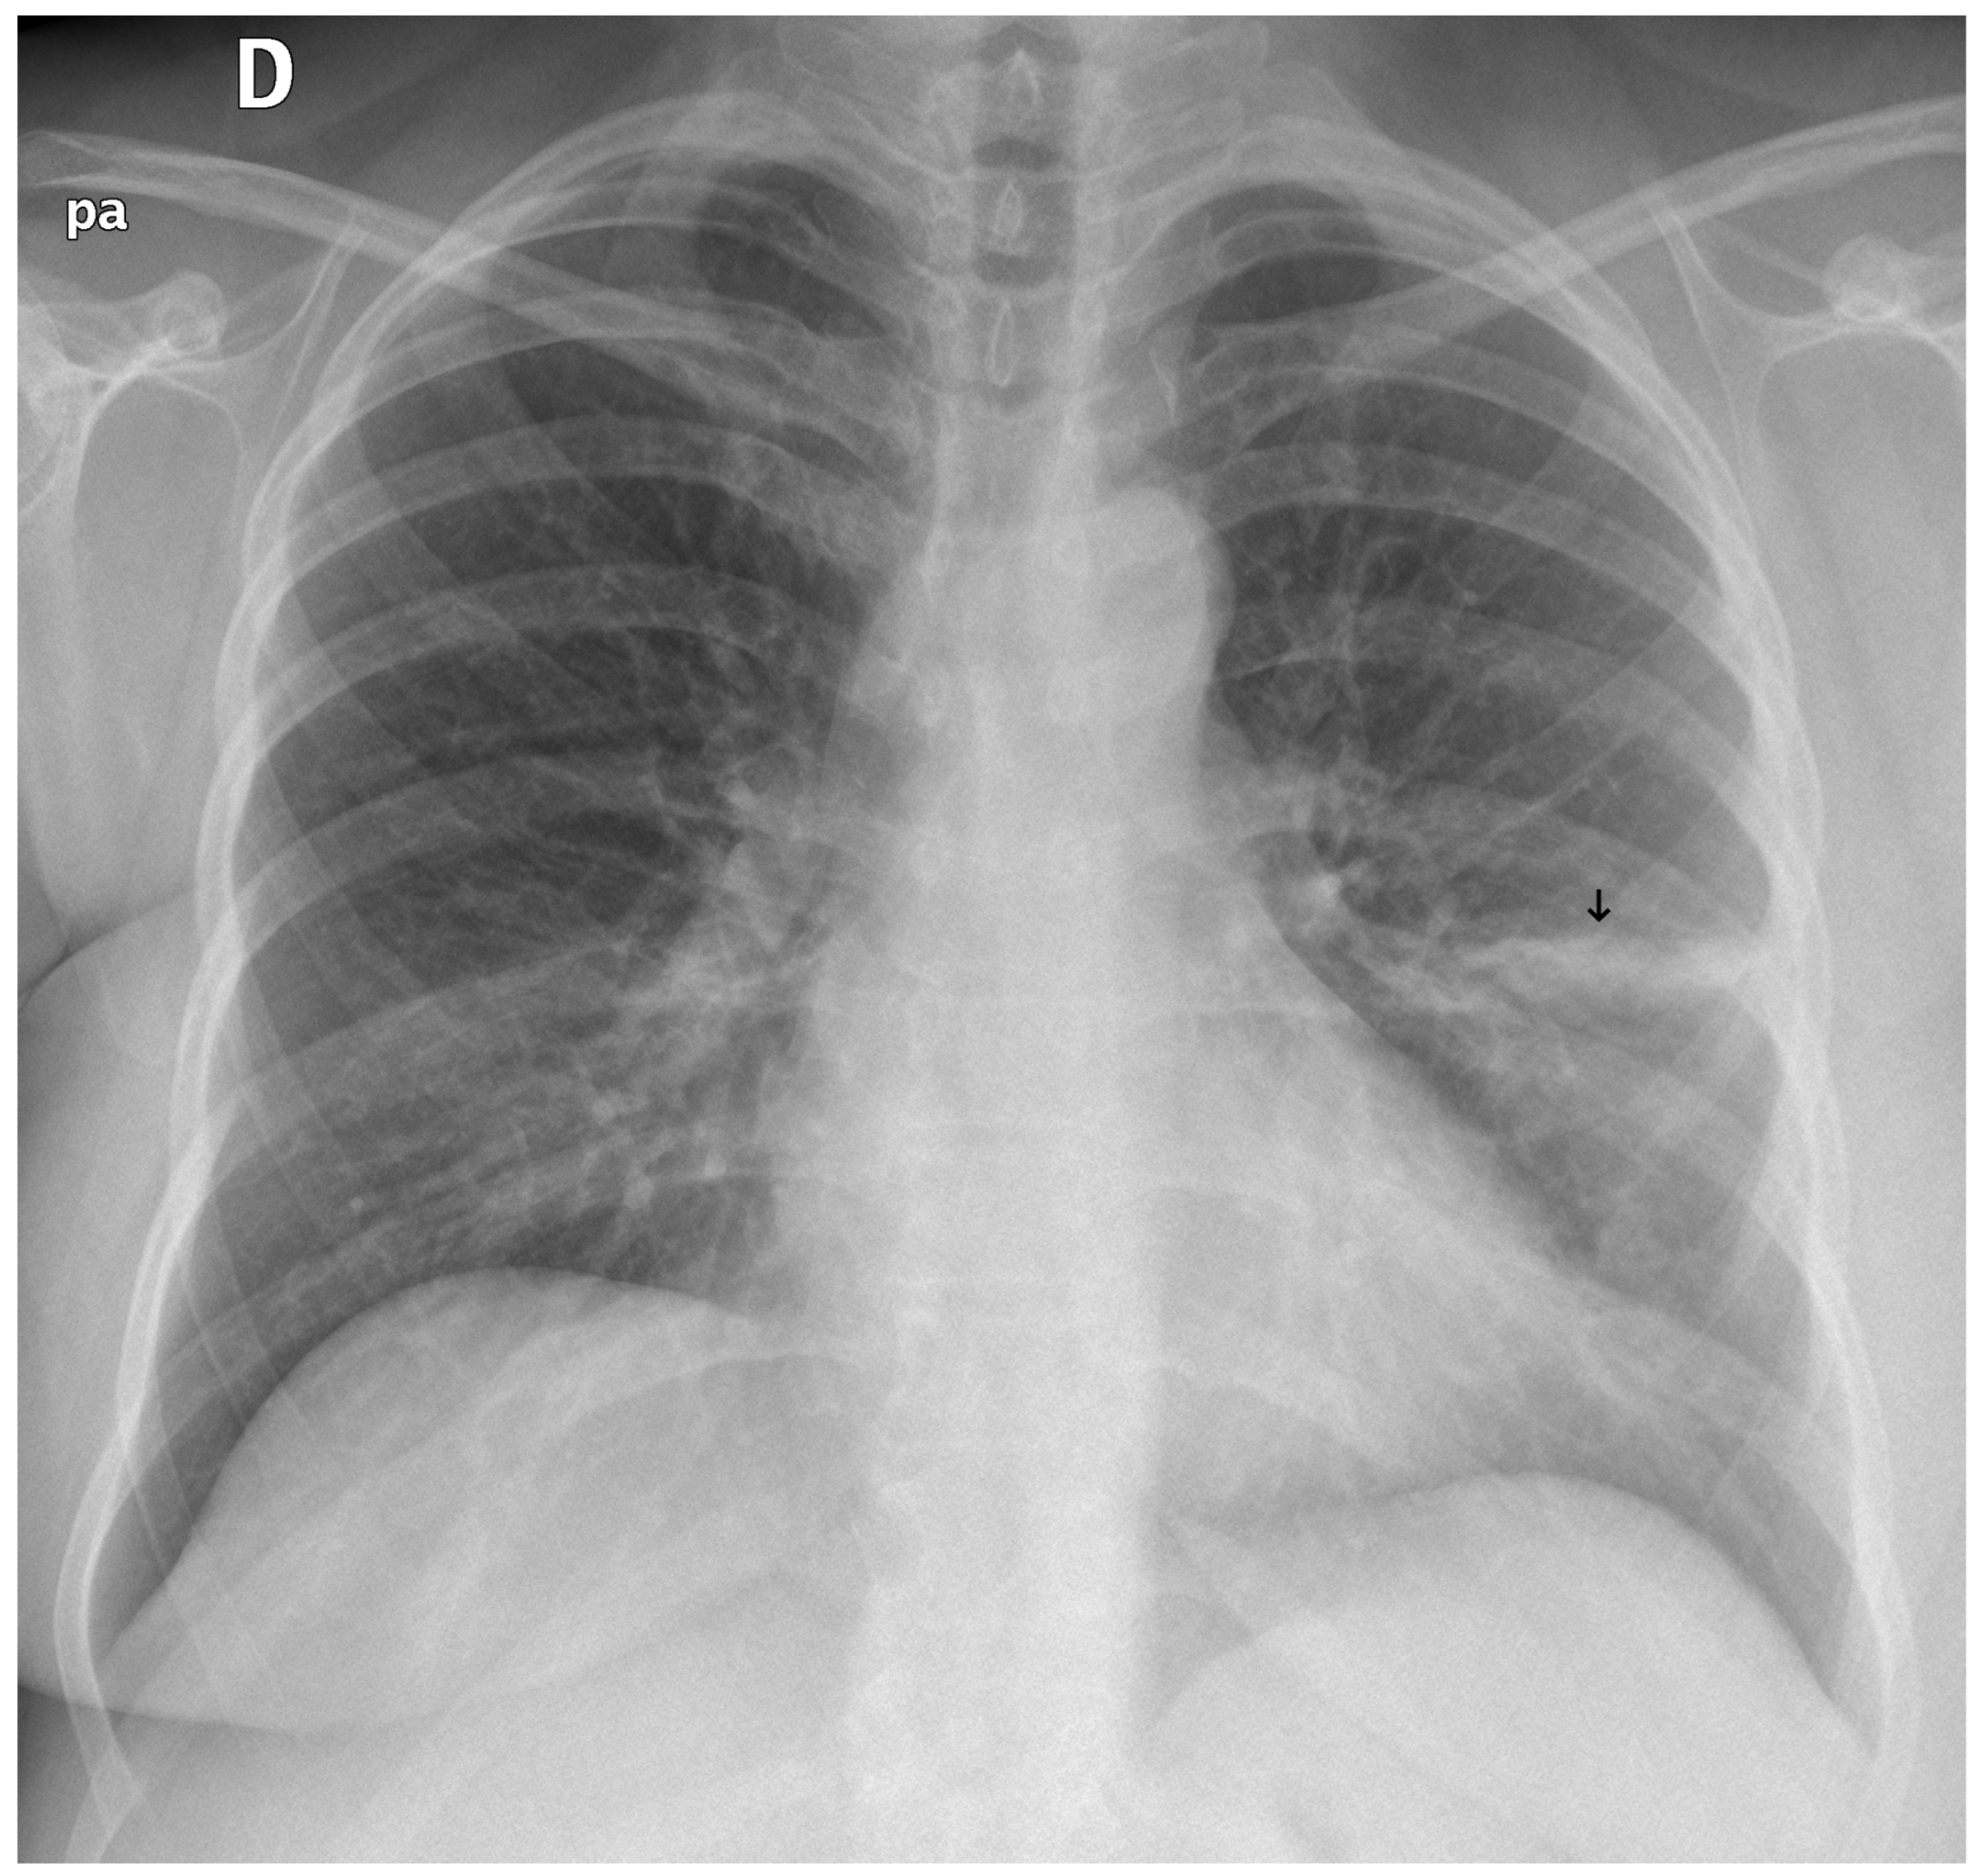

3.3. Error Analysis

An analysis of the algorithm’s false negatives revealed a nuanced performance profile, where a specific miss did not always equate to a complete system failure. Across the board, a substantial number of cases with a false negative for a particular pathology were nevertheless correctly identified as abnormal by the general “yes-finding” classifier or had other co-occurring true positive pathologies. For example, out of 38 false negatives for opacity, the algorithm correctly identified the exam as abnormal in 25 cases. In many instances of a missed finding, the algorithm successfully detected other pathologies within the same study. Misclassification was another notable source of error, where an existing pathology was detected but incorrectly labeled, such as opacities being predicted as masses or nodules (Figure 4). Radiologist review of these false-negative cases frequently noted findings that were “subtle,” “small,” “doubtful,” “seen on lateral image only,” or “non-specific.” In other cases, the algorithm correctly identified a more critical finding, like a large pleural effusion, while missing a secondary, less significant pathology (Figure 3). Figure 9, Figure 10 and Figure 11 illustrate false negative cases for opacity, pneumothorax, and nodule, respectively. This highlights the inherent limitations and inevitable failures of this kind of system.

Figure 4. A true positive example of a nodule/mass (left) and its bounding box generated image (right). In this case, the report indicated opacity; however, the algorithm classified as a mass.